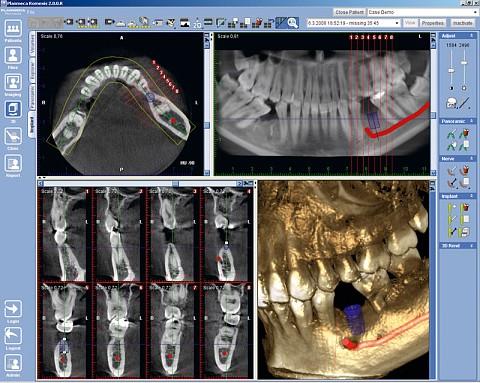

3D Снимок

Это самая показательная и точная диагностика, которая позволяет изучить строение зубов и челюстных тканей в трехмерном формате в касательной, осевой и фронтальной проекциях. Проблемный участок можно рассмотреть в нужной плоскости под любым углом. Диагностика выполняется на компьютерном томографе (последовательная съемка в разных плоскостях низкодозированным рентгеновским облучением в различных плоскостях с последующим преобразованием в полноценное трехмерное изображение) и позволяет получить достоверную картину:

• строения сосудов;

• состояния мягких тканей десны;

• состояния корней (обнаружение трещин, кист и т.д.);

• структуры костной ткани, ее плотности;

• состояния твердых тканей зуба (наличие кариеса) и др.

У этого метода нет недостатков, кроме более высокой стоимости, которая оправдывается информативностью и точностью диагностики.